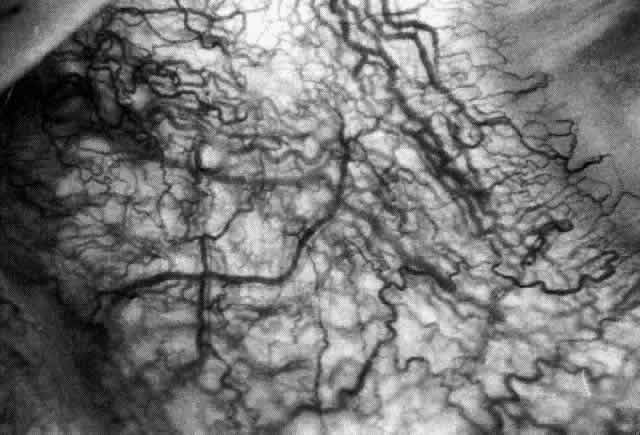

and adequate treatment can prevent these changes from becoming irreversible.  Fig. 27. In scleritis, maximum congestion occurs in deep episcleral plexus, which

is bowed forward by underlying scleral edema. Episcleral tissue is slightly

infiltrated and superficial plexus is slightly congested (see Fig. 14). (Watson PG, Hayreh S, Awdry P: Episcleritis and scleritis. Br J Ophthalmol 52:278–279, 1968) Fig. 27. In scleritis, maximum congestion occurs in deep episcleral plexus, which

is bowed forward by underlying scleral edema. Episcleral tissue is slightly

infiltrated and superficial plexus is slightly congested (see Fig. 14). (Watson PG, Hayreh S, Awdry P: Episcleritis and scleritis. Br J Ophthalmol 52:278–279, 1968)

|